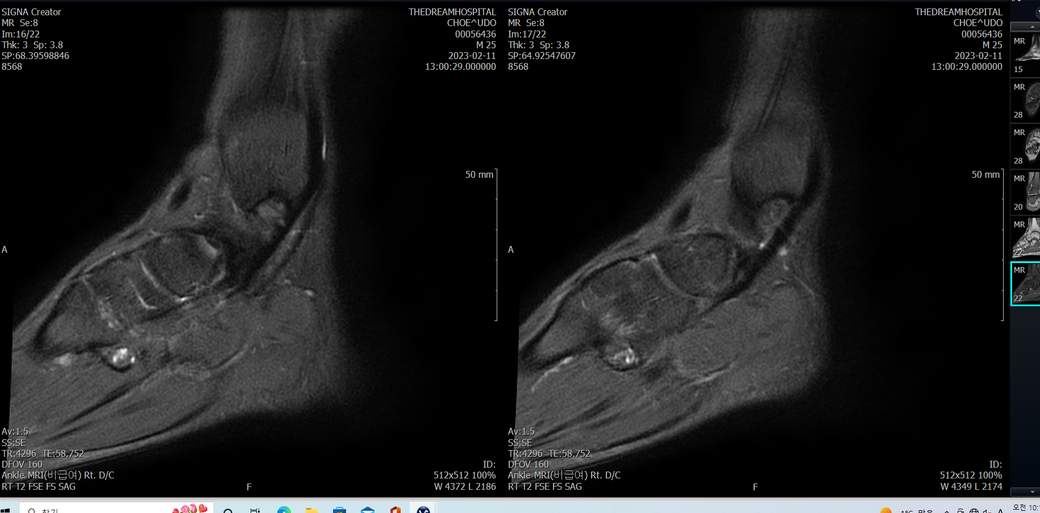

발목 mri 한번 봐주실수 있을까요?

오른발목 mri 전체사진입니다. 제가 병원을 갈수없는상황인지라.... 봐주시면 감사하겠습니다.

엑스레이에서는 문제가 없다고 하여 오른발목 mri촬영했습니다.

우선 전반적으로 봤을 때 큰 이상은 없어보입니다.

전거비인대 등도 저명한 손상은 없는 것 같아 보이지만, 어느 부분의 통증 등으로 인해 촬영을 하셨는지 말씀을 해주신다면 보다 정확한 병변파악이 가능하겠으며, 병원에서 판독이 완료되신다면 전화 등으로 문의를 해보시는 것이 좋겠습니다.